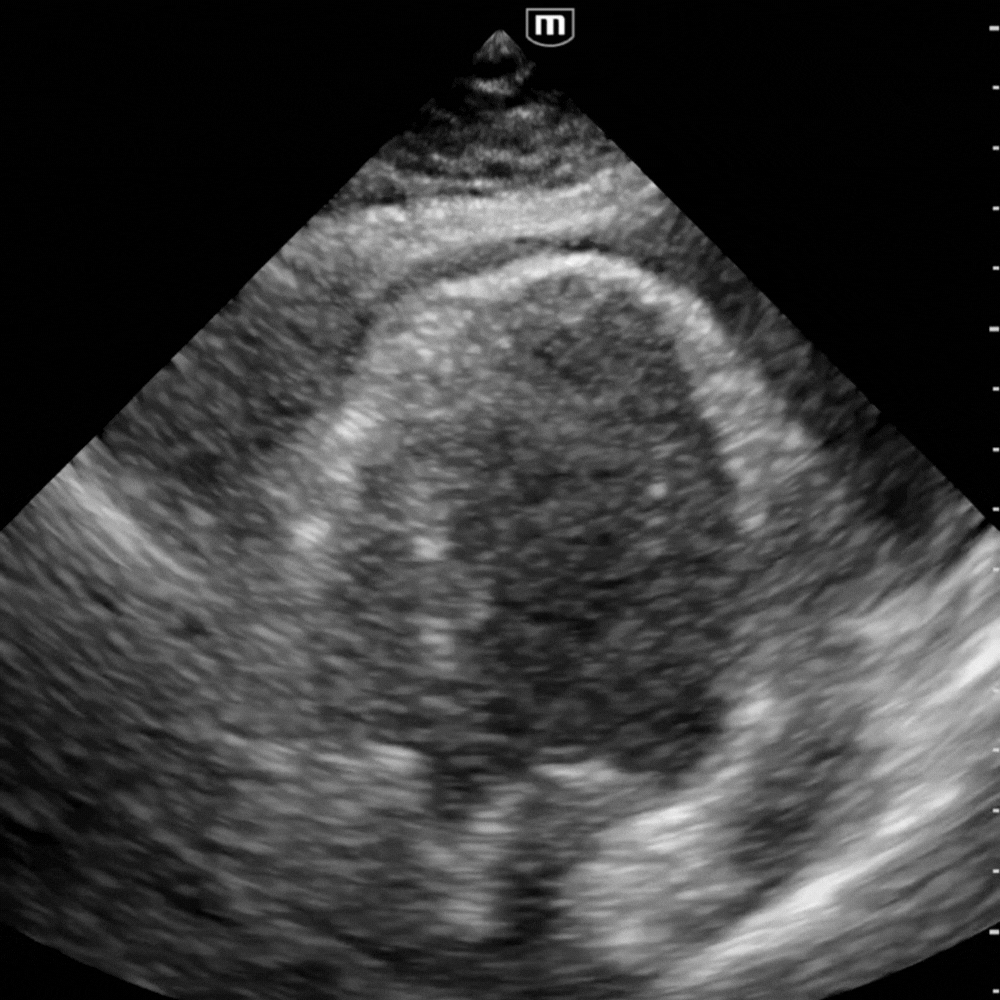

Vue apicale quatre cavités

Montre la circonférence du liquide et le balancement du cœur (“swinging heart”) lorsque le volume est important.

Vue utile pour juger la cinétique globale et confirmer le collapsus diastolique du VD.

⚙️ 4. Interprétation hémodynamique

Mesurer la lame péricardique toujours en fin de diastole, perpendiculairement au myocarde, sur la coupe où elle apparaît la plus large.

- Épanchement minime : film noir postérieur < 10 mm, sans retentissement.

- Épanchement modéré : entoure partiellement le cœur, mesure 10-15 mm, gêne au remplissage possible.

- Épanchement massif : contourne complètement le cœur, mesure > 15 mm, cœur flottant, collapsus droit net.